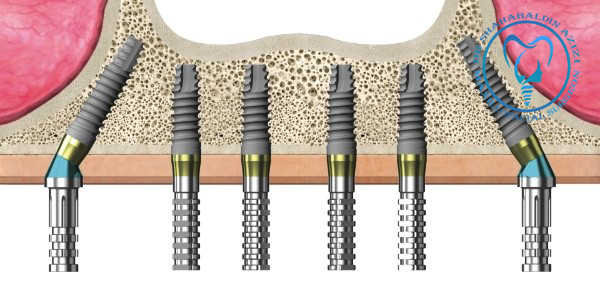

تاثیر سلامت لثه در موفقیت ایمپلنتهای دندانی ایمپلنتهای دندانی یکی از پیشرفتهترین و موثرترین روشها برای جایگزینی دندانهای از دسترفته هستند. این روش شامل کاشت پایهای تیتانیومی در استخوان فک و قرار دادن تاج دندان بر روی آن است. موفقیت و ماندگاری ایمپلنتها تا حد زیادی به سلامت لثهها بستگی دارد. لثهها نه تنها به…